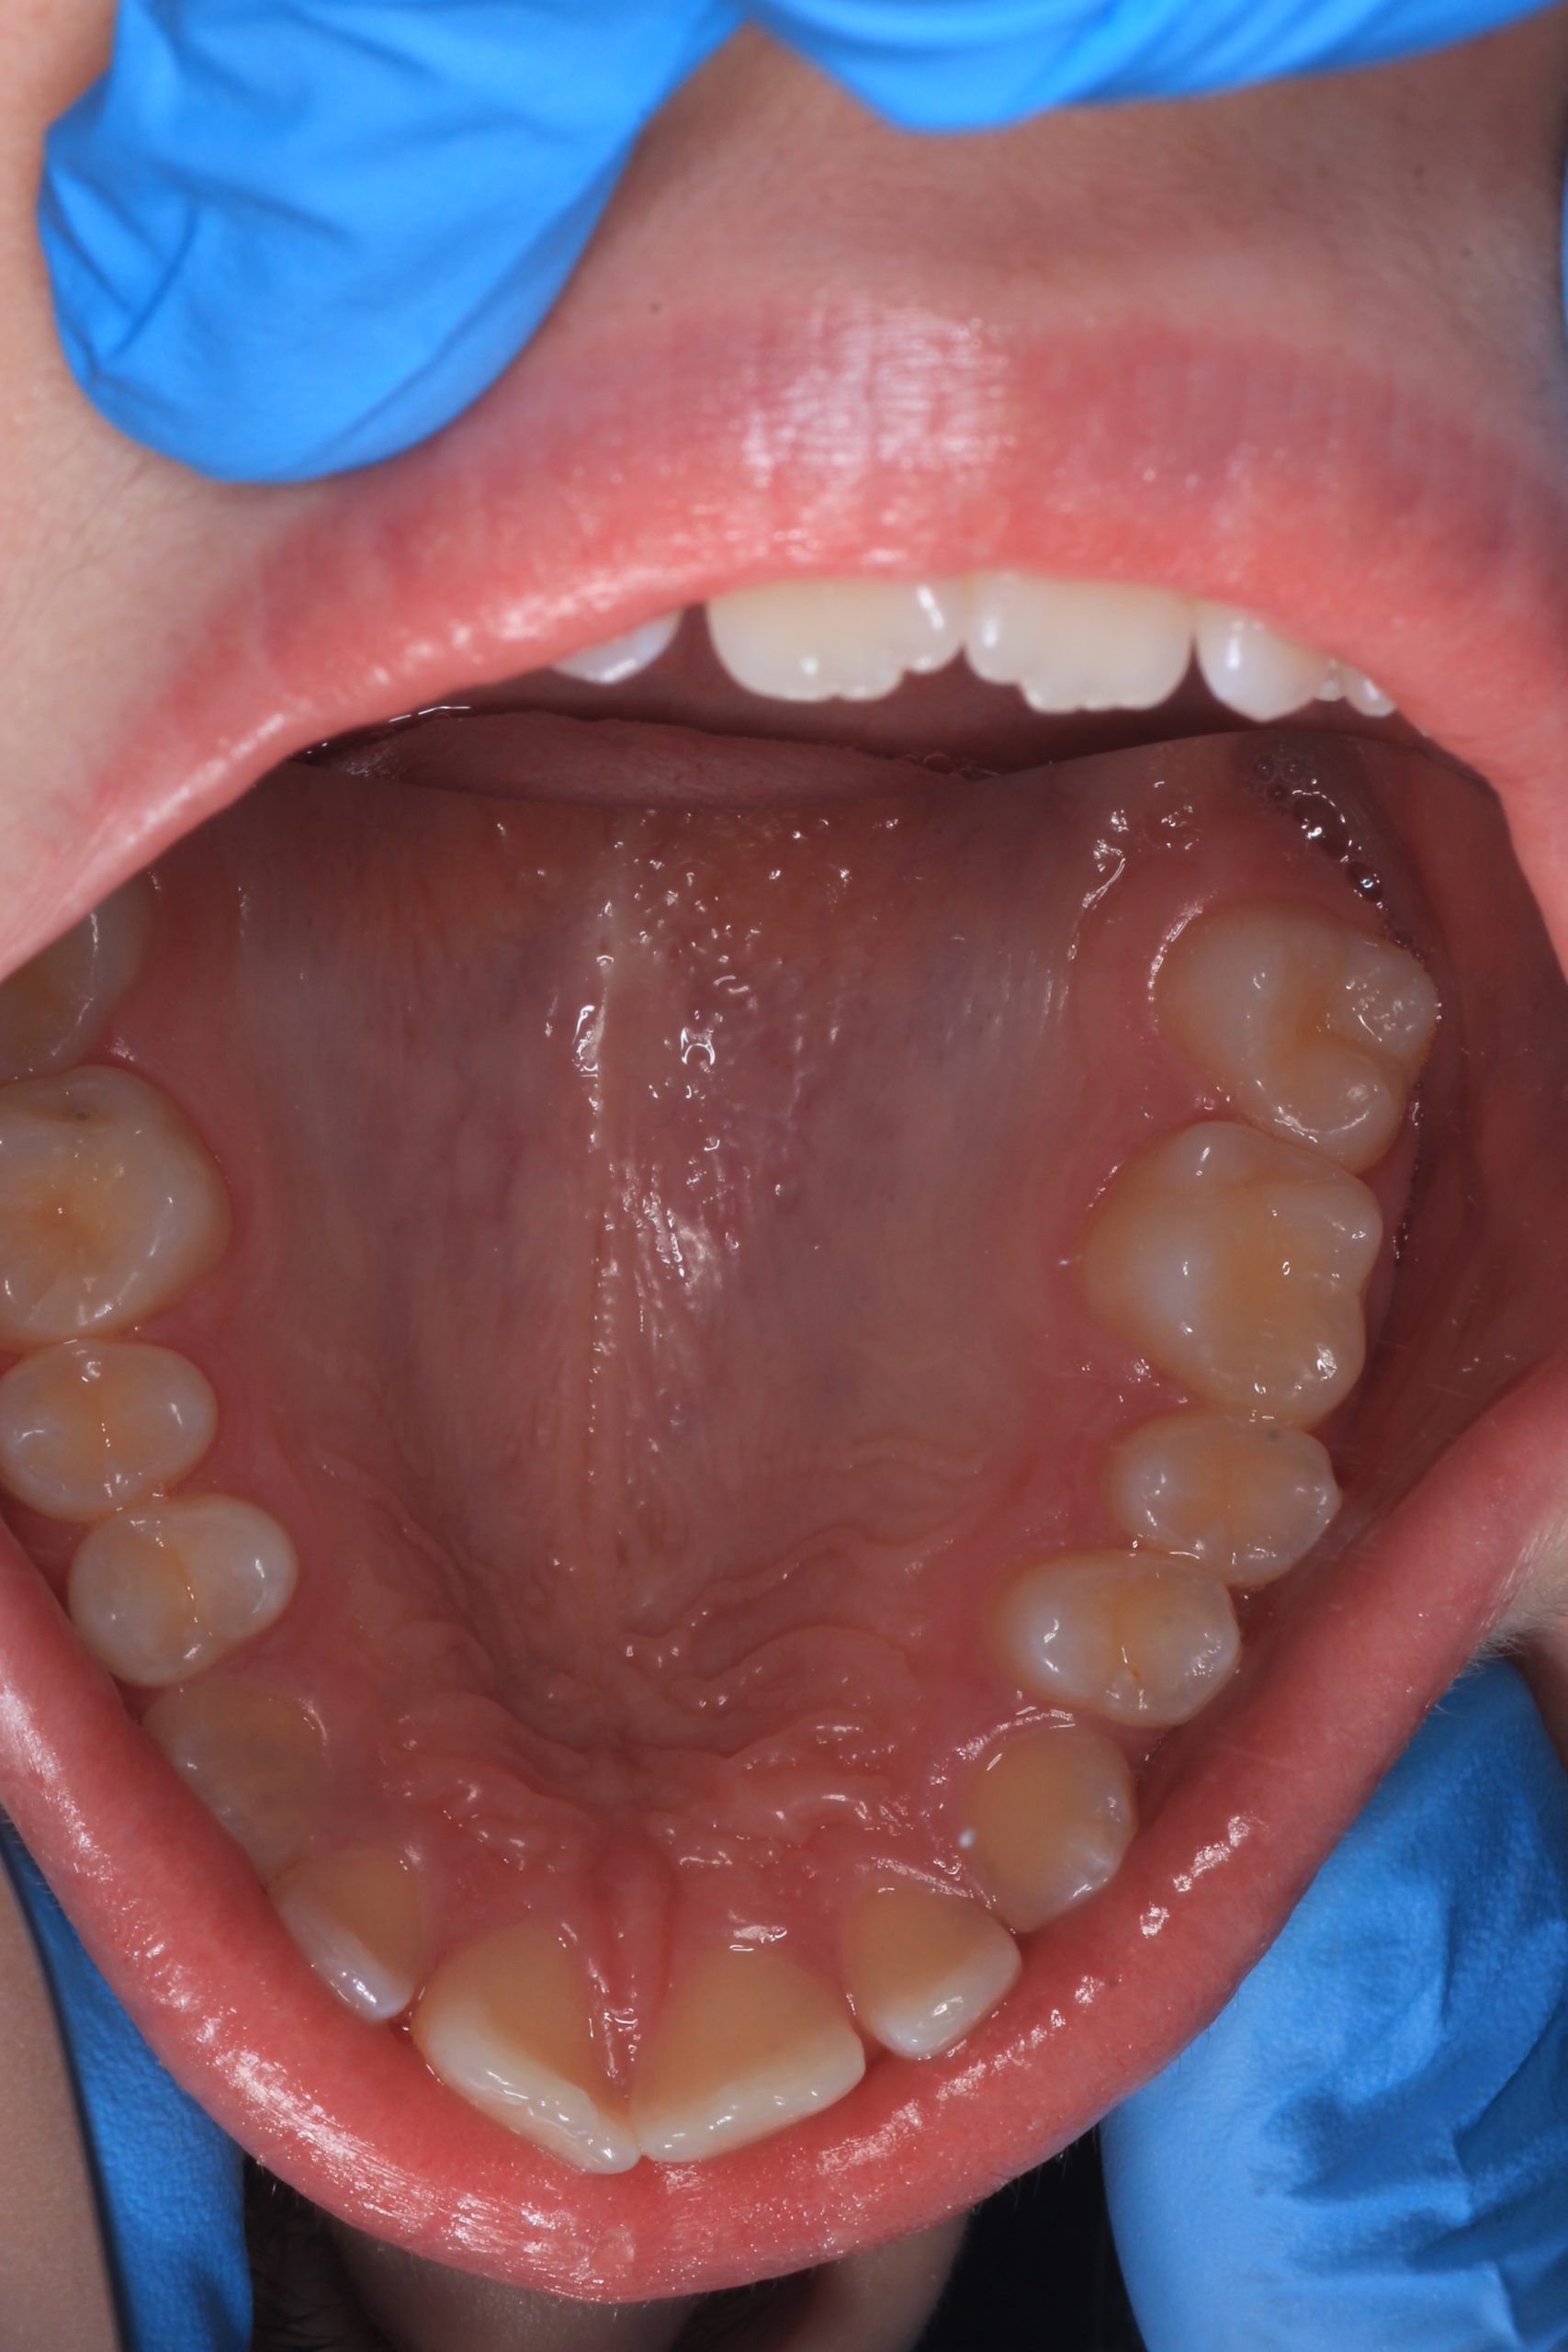

We examine the condition of teeth, gums, and bite. - Plaque Disclosure with Special Indicators

Areas that weren’t cleaned well appear purple. The darker the shade, the older the plaque. This helps both kids and parents understand where brushing needs to improve. - Brushing Training & Home Care Tools Selection